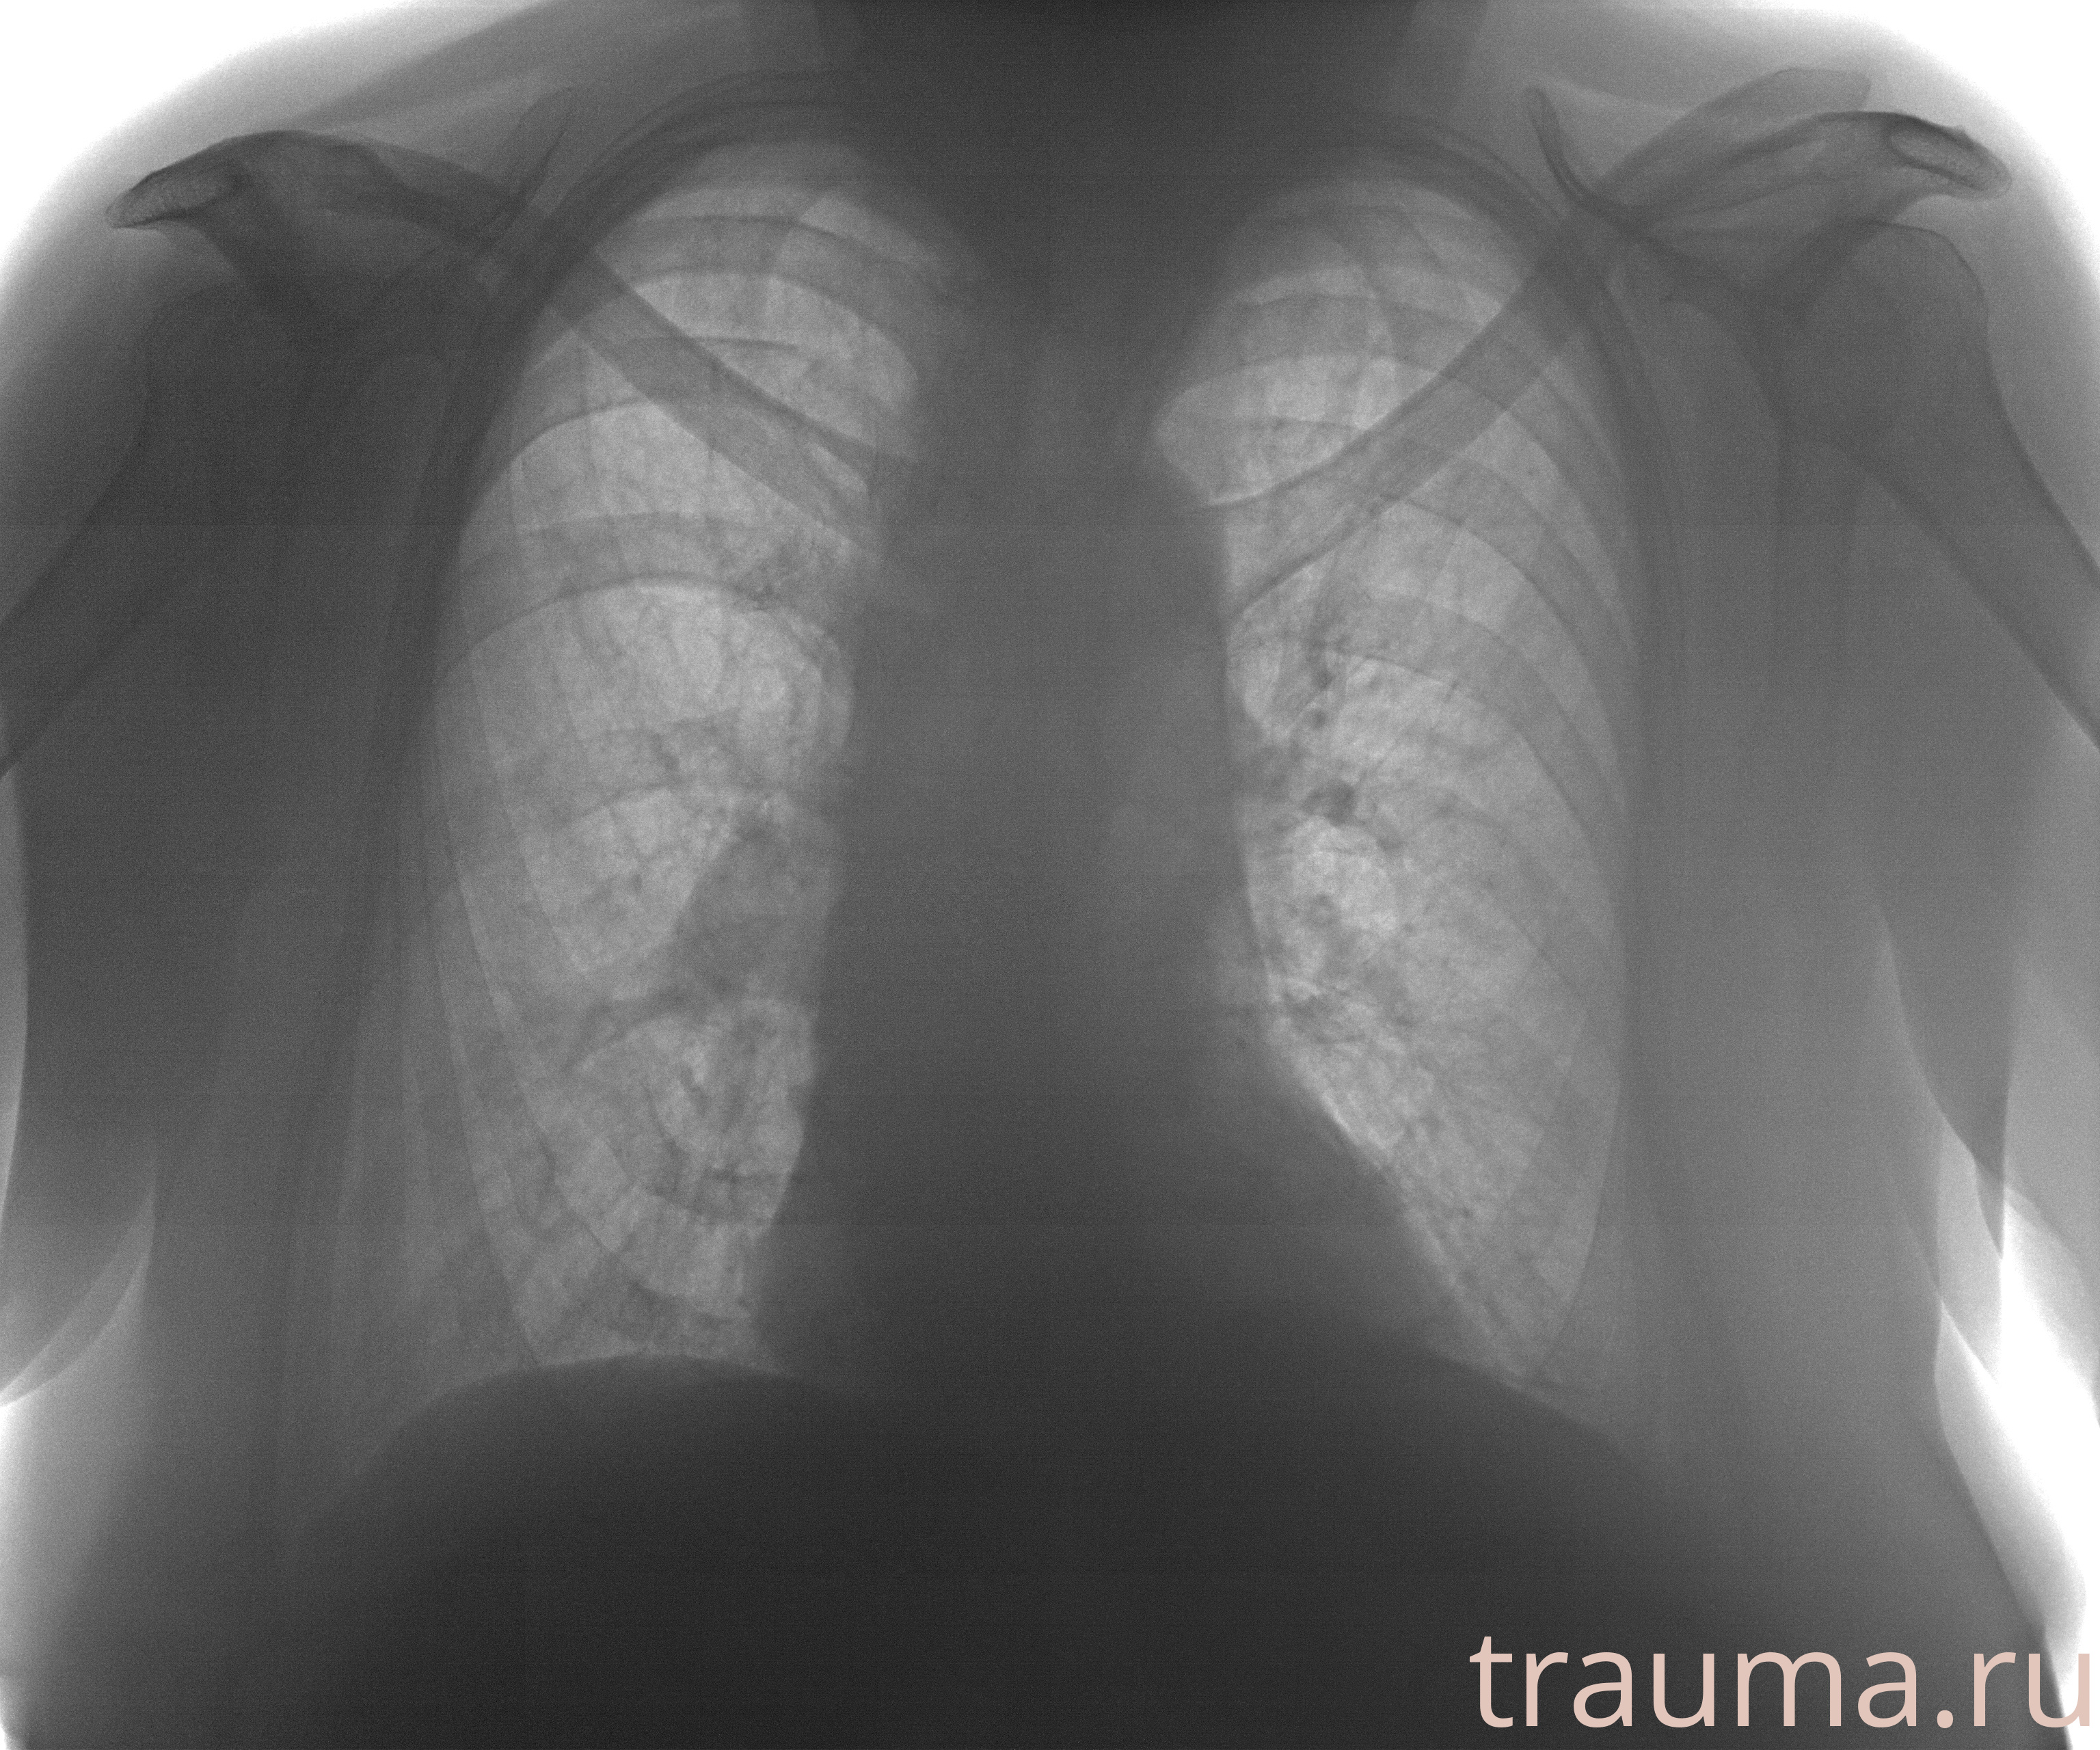

Рентгенограммы

Рентген на дому: по вашему адресу приезжает врач-рентгенолог, травматолог-ортопед с мобильным рентгеновским аппаратом, проводит диагностику травмы или заболевания, делает необходимые рентгенограммы, дает рекомендации по дальнейшему лечению. Получить качественные снимки в домашних условиях возможно благодаря уникальной методике, разработанной МосРентген Центром для института  Склифосовского

Яркость: 1   Контраст: 1   Инвертировать: 0 Увеличение: 1

Перетаскивайте мышь вверх/вниз для контраста, влево/право для яркости. Прокрутка колесом изменяет масштаб. Нажмите Сбросить для возврата к исходному изображению. При увеличении держите мышь в той области, которую хотите рассмотреть.

при переломе шейки бедра и пневмонии от компании МосРентген Центр - партнера Института имени Склифосовского